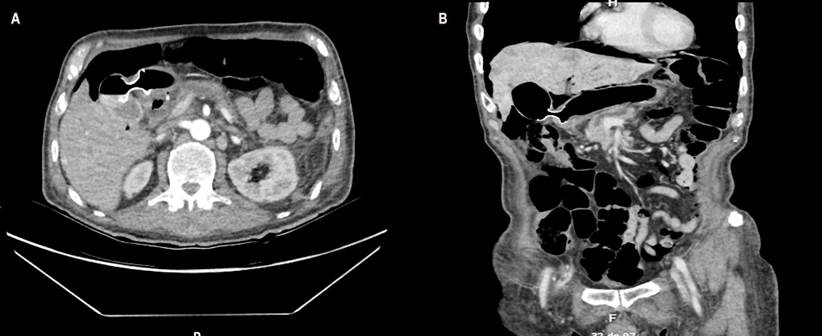

A 69-year-old male patient with a history of inoperable metastatic pancreatic neuroendocrine tumor and who had experienced abdominal pain, hyporexia, jaundice, and choluria for 15 days was admitted to the institution. A cholangioronance was performed in which a 5 cm mass in the head of the pancreas blocking the bile duct was observed. A dilated cystic duct was also identified (Figure 1).

In our case, EUS-guided choledoduodenostomy could not be performed due to duodenal invasion. Furthermore, magnetic resonance cholangiopancreatography showed that the gallbladder was distended (Courvoisier-Terrier sign) and communicated well with the extrahepatic bile duct. Therefore, EUS-guided cholecystogastrostomy was chosen instead of EUS-guided hepaticogastrostomy9,12-14.